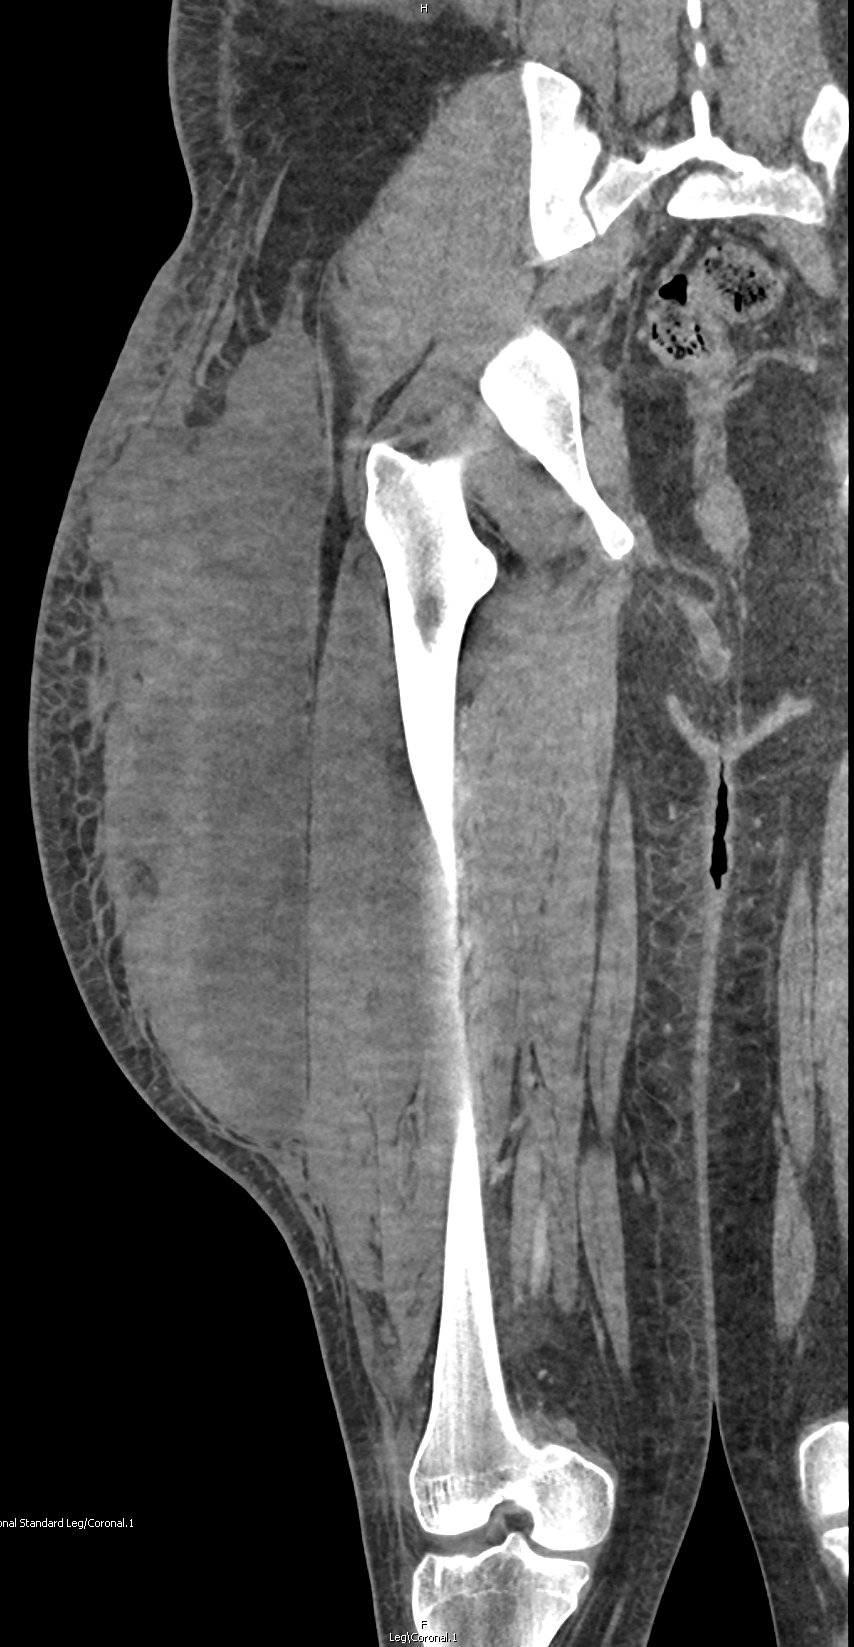

On physical examination, he was noted to have a nearly “watermelon-sized” fluctuant mass to his right lateral superior quadriceps with multiple overlying abrasions (Image 1). Computed tomography (CT) scans of the area showed a large heterogeneous collection measuring roughly 37×9.5×16 centimeters in the subcutaneous adipose layer of the lateral right thigh (Image 2), while ultrasonography revealed a complex fluid collection containing some nodular solid components and debris (Image 3). Additionally, radiographs confirmed multiple fractures including most significantly a pelvic ring fracture. Surgical debridement, evacuation, and sclerodhesis were performed nine weeks post injury to allow overlying abrasions to heal prior to intervention.